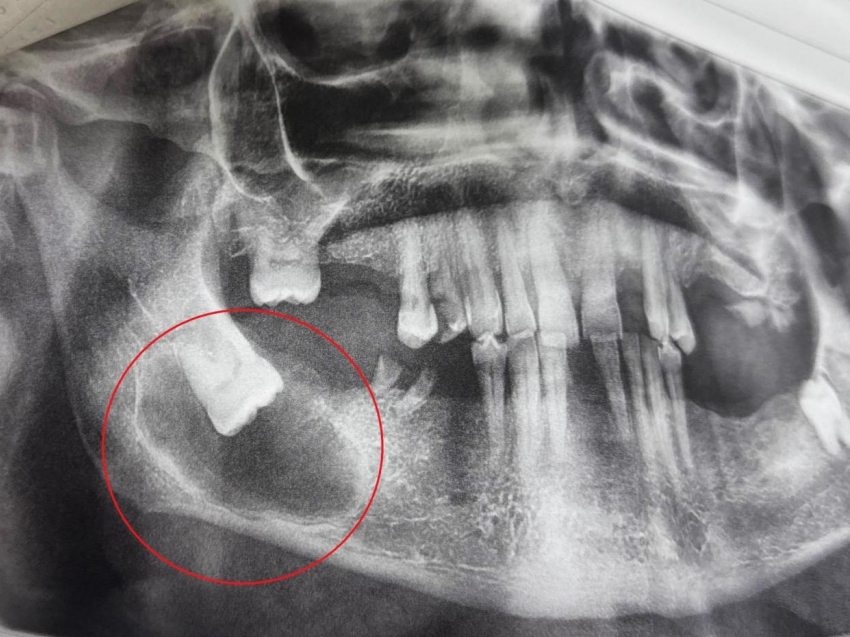

При осмотре врачи заметили покраснение слизистой и небольшую припухлость за последним зубом, но главный сюрприз преподнесло рентгенологическое обследование.

Оказалось, что причиной дискомфорта стал ретинированный (то есть непрорезавшийся) зуб мудрости. Он расположился в кости совершенно нетипично - горизонтально, словно «лежа» на боку. Более того, вокруг его коронки и части корня сформировалась фолликулярная киста. Новообразование привело к истончению костной ткани и кортикальной пластинки, что и вызывало у пациента чувство распирания.

Сложную операцию провела стоматолог-хирург Анастасия Асеева. Под местной анестезией хирург получила доступ к проблемной зоне: после разреза и отслоения лоскута ткани была обнажена истонченная кость. Медики выполнили трепанацию (создали отверстия) и удалили злополучный зуб мудрости.